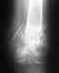

несросшийся перелом локтевого отростка после остеосинтеза диастаз 3мм по КТ и МРТ |

У меня 15 мая перелом локтевого отростка со смещением носил гипсовую лонгету операцию остеосиетеза по Веберу сделали 7.06 через месяц появилась стабильная субфебрильная температура. 17.08 в травм отделении госпитале ветеранов войн срочно убрали металоконструкцию т.к.по КТ сустава спицы проходили через сустав. Кстати, диастаз был 3 мм 25.08 сделал МРТ сустава - диастаз 3 мм неконсолидированный в/суставной перелом. Подскажите, что мне делать

30 августа был на консультации НИИ травматологии у травматолога Медведевой, пожаловался на субфебрильную температуру. 3 месяца прошло, 2 срока после остеосинтеза. Металоконструкция убрана 17.08 в госпитале ветеранов войн т.к спица пробила сустав. Мне сделали КТ. Сказали, что остеомиелита нет. Диастаз при разогнутой руке 3 мм. Костных балок нет, есть хрящевая ткань по краям. Руку не фиксировали, сказали ограничить физические нагрузки. Работаю врачом неврологом в Первоуральске. Пишу, печатаю, осматриваю пациентов. Субфебрильная температура держится если нужна повторная операция, я согласен платно. Сколько это стоит и как практически это сделать в НИИ травматологии. Подскажите очень буду благодарен, не знаю, что делать?